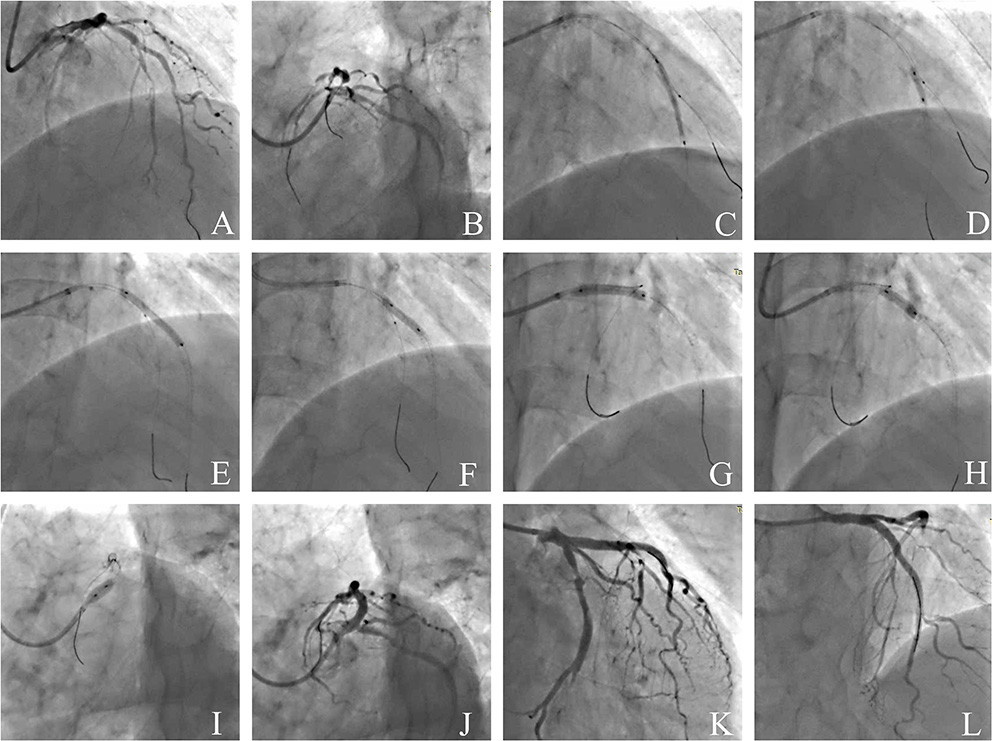

Representative Case of JB-POT Application

Figure 7 shows a representative case of JB-POT application in a coronary bifurcation lesion with risked SBs. Baseline coronary angiography LAD had diffused stenotic lesions from medium LAD to LAD ostium branching 2 diagonal branches and 1 septal branch. LAD-D1 was below 2 mm, and its territory was limited; hence, LAD-D1 did not need to be protected during the procedure. The other 2 bifurcation lesions were both Medina classifications (1,1,1). Baseline angiography showed both bifurcation lesions had a narrow carina angle and a short branching point-carina tip complying with carina length mismatch (18), which was demonstrated to be highly related to SB compromise after MV stent crossover implantation (21). Two sequential JB-POT procedures were performed sequentially on the LAD-D2 and LAD-S1 lesions, as shown in Figure 7. A third stent was then deployed in the proximal LAD-LM with a wire jailed in the LCX because the LCX was thought to be safe during stent crossover. Postprocedure IVUS examination showed that the stents had quite satisfactory apposition and expansion after JB-POT interventions. The struts just proximal to the branching point also showed good apposition and expansion, although they were avoided by re-POT (Figure 8). The whole procedure protected 3 SBs (1 diagonal branch, 1 septal branch and 1 LCX) by the same guide wire, costing only 40 min, 100 ml of contrast media and 350 mGry X ray radiation. No rewiring and kissing were required.

Figure 7

Coronary angiography illustrating the JB-POT in the intervention of a complicated bifurcation lesion. (A,B) Baseline angiography of diffused LAD-LM lesions with 3 true bifurcations (LAD-D1, LAD-S1, LAD-D2); (C) deploying a 2.5 × 29mm DES crossing D2 with a 1.5 × 15mm balloon jailed in D2; (D) post-dilation and JB-POT of the first stent with 2.5 × 12mm and 3.0 × 12 non-compliant balloons; (E) deploying a 3.0 × 29mm DES crossing D2 with a 1.5 × 15mm balloon jailed in D2; (F) JB-POT of the 3.0 stent with a 3.5 × 12 NC balloon, re-POT the 2.5mm stent and post-dilation of the 3.0mm stent with a 3.0 × 15 NC balloon; (G) deploying a 3.5 × 24mm DES crossing LCX with a wire jailed in LCX; (H) post-dilation of the 3.5mm stent and re-POT of the 3.0mm stent with a 3.5 × 12 NC balloon; (I) performing POT in LM with a 5.0 × 10 NC balloon; (J–L) final angiographic results. JB-POT, jailed balloon proximal optimization technique; LAD, left anterior descending coronary artery; LM, left main coronary artery; D1, the first diagonal -branch; D2, the second diagonal branch; S1, the first septal branch.